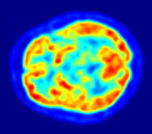

FluorodesoxiglucosaLa fluorodesoxiglucosa (2-fluoro-2-desoxi-D-glucosa, FDG) es un análogo de la glucosa y se incorpora en células con gran consumo de glucosa (cerebro, riñón, células cancerígenas, …).El flúor de la FDG puede convertirse en flúor-18, un isótopo radiactivo emisor de positrones. El oxígeno del C2 es necesario para la glucólisis, por lo que la FDG no puede ser metabolizada antes de que decaiga la radiactividad y el 18F se convierta en 18O y la FDG se convierta en glucosa-6-P, ya metabolizable.Por ello, es muy utilizada en el diagnóstico médico por imagen, concretamente en la modalidad de tomografía por emisión de positrones (TEP).Quora